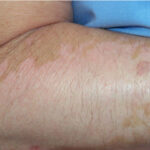

Patients with vitiligo present with one to several amelanotic macules that appear chalk- or milk-white in color. The lesions are usually well-demarcated, but the margins may be scalloped. They are accentuated on Wood's lamp examination. Lesions enlarge centrifugally at an unpredictable rate and can appear on any body site, including mucous membranes. However, initial lesions occur most frequently on the hands, forearms, feet, and face. When vitiligo occurs on the face, it often favors a perioral and periocular distribution.

Koebnerization commonly occurs in vitiligo. Lesions frequently develop at sites of trauma, such as mild friction from clothes, or from a cut, burn, or abrasion .

Depending on ethnic color, vitiligo is more or less conspicuous .